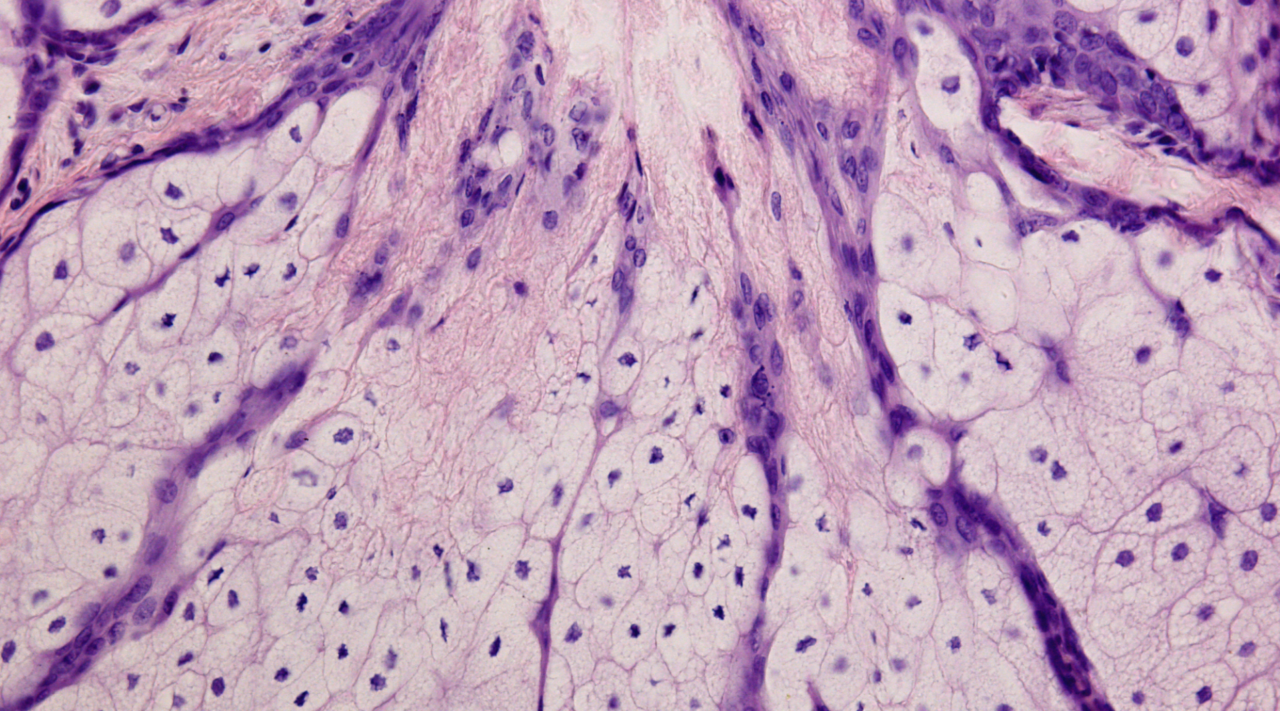

イソトレチノインは、皮膚細胞や皮脂腺細胞を正常化する働きがあります。皮膚の細胞が正常になることで、皮膚が厚くなり、毛穴が詰まる現象が起こらなくなります。そのため、毛穴が詰まりにくくなり、にきびが発生しにくくなります。

イソトレチノインは抗生剤ではありませんが、皮脂腺を退縮させ、皮脂分泌を大きく減らす作用があり、これにより、にきびの原因菌であるアクネ菌が生着できなくなり、抗生物質よりもアクネ菌の数を減らすことができると言われています。